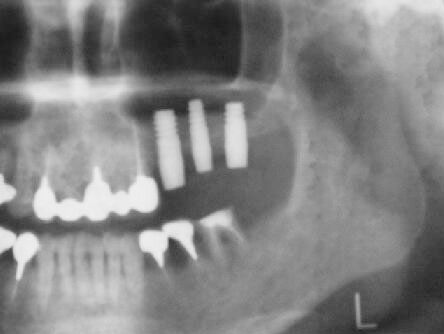

術前エックス線写真と口腔内写真

この方も上顎洞の下縁の骨が1〜3ミリ程度しかなくソケットリフトでは不可能なのでサイナスリ フトの選択となる